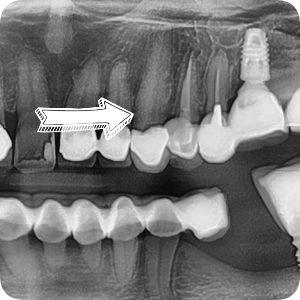

화살표가 가르키는 치아를 봐주세요.

크라운과 치아 사이의 경계가 깨~끗합니다.

그!러!나!

잇몸치료를 위해 마취를 하고 치석을 박박 긁어내던 순간......!!

크라운 하방에 기구가 걸리는 것이 느껴집니다.

원래 크라운 밖에서 보였던 충치는 아래 화살표 방향이었는데,

크라운을 제거해보니 왼쪽 화살표가 가리키는

더욱 큰 충치가 발견되었습니다.

다행히 충치가 신경까지 이어지지 않아,

충치가 제거된 빈 공간을 단단한 레진으로 매꾸고

새로운 옷(=크라운)을 입혀줄 준비를 합니다.